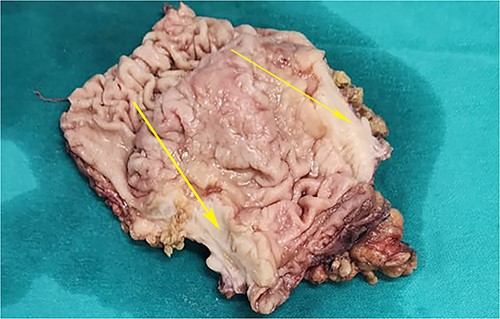

On laparotomy, the gastric antrum was infiltrated with a tumour with no serosal extension (Fig. 4), no ascites, and bilateral ovarian cysts (right: 12 × 10 × 6 cm, left: 9 × 5 × 4 cm) (Fig. 5). An R0 resection that included D2 gastrectomy and pan-hysterectomy was performed. The patient made an uneventful recovery and was discharged on the 15th postoperative day. The final diagnosis after histopathological examination was diffuse infiltrating gastric carcinoma signet cell-type (Figs 6 and 7), LP, KT deposits in both the ovaries (Fig. 8), with regional lymph node involvement (Fig. 9) in two nodes among the 15 nodes that were dissected. The staging was T4a, N1, and M1. The patient decided against adjuvant treatment. She was disease-free on clinical and radiological examinations at 12 months.

Postoperative specimen of the stomach showing intramural tumour at the pyloric antrum (arrow).

Postoperative specimen of the right ovarian cyst showing solid areas within (arrows).